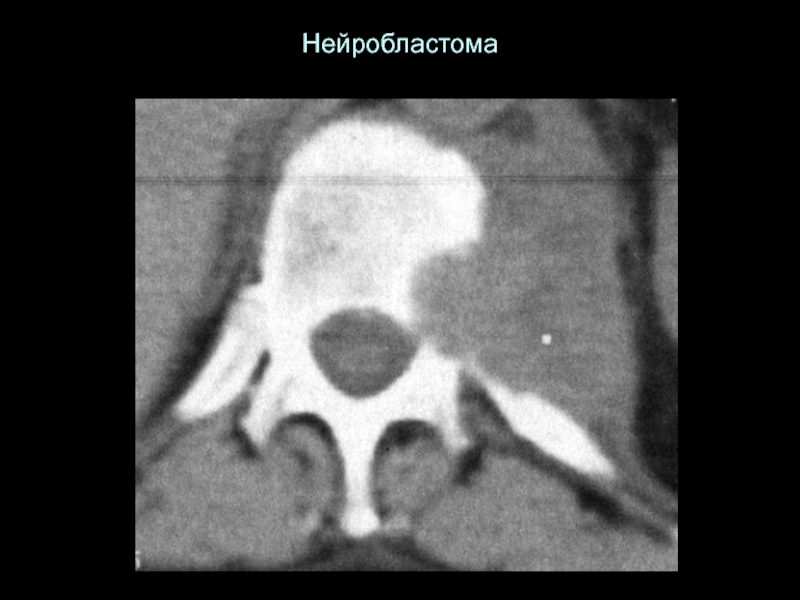

Слайд 33Нейробластома

Нейробластома

Слайд 47Нейробластома